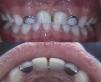

Al examen clínico intraoral se observa dentición primaria completa, ausencia de los dientes 5.1 y 6.1, gingivitis margino-pailar localizada asociada a placa bacteriana, resto de los tejidos blandos de aspecto normal, sin actividad de caries, escalón mesial bilateral, relación canina clase i e interposición lingual como consecuencia de la pérdida dentaria (figs. 1 y 2).

La figura 5 muestra una vista frontal y palatina de la prótesis a los 12 meses de seguimiento, donde se destaca un aumento del espacio interincisivo de aproximadamente 1,5mm, lo que demuestra el crecimiento en sentido transversal. Es importante mencionar que la prótesis tiene fines estéticos, actúa de forma pasiva, por lo que no ejerce ninguna acción sobre los tejidos dentarios u óseos. Cualquier modificación en la oclusión está solo dada por el crecimiento maxilofacial normal del preescolar.